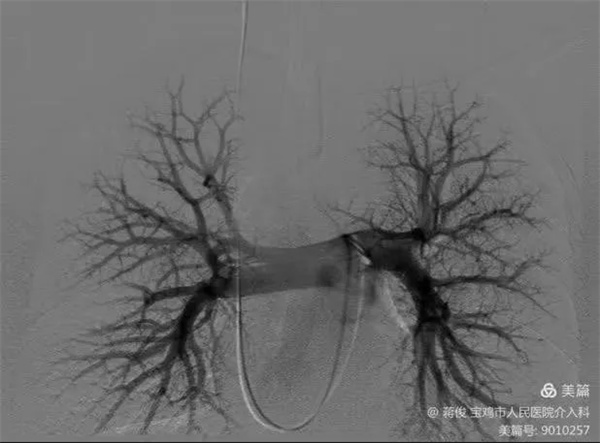

5.webp.jpg

規律抗凝半年后,復查肺動脈DSA造影提示肺動脈血栓完全消除,同期取出下腔靜脈濾網

6.webp.jpg